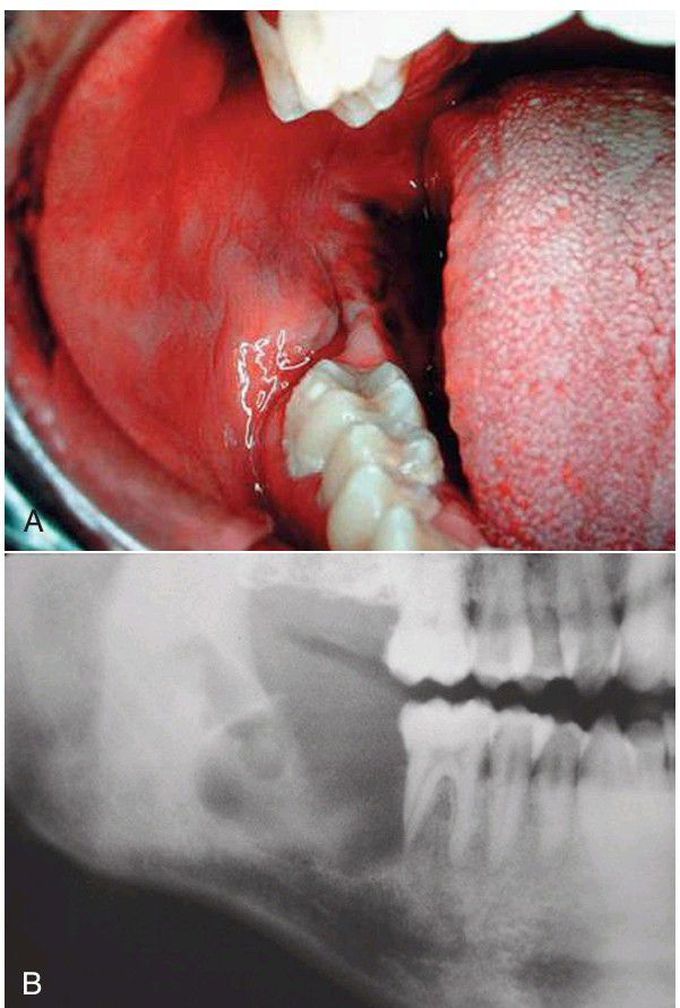

Mucoepidermoid carcinoma

A) Central mucoepidermoid carcinoma of the right retromolar pad of minor salivary glands (note bluish appearance). (B) The panoramic radiograph shows the underlying multilocular radiolucency